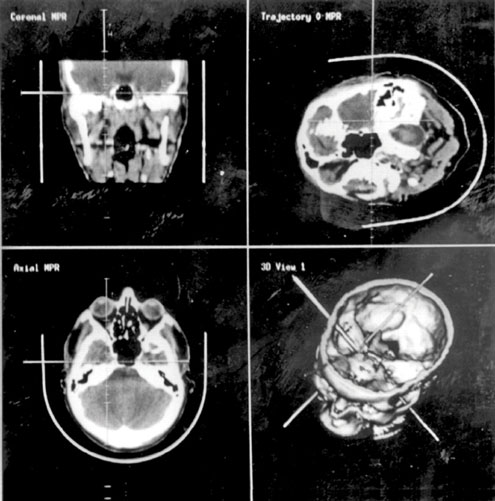

A técnica da neuronavegação é uma delas. O método moderno se baseia no mapeamento tridimensional do cérebro, com o auxílio de um microscópio de última geração que projeta uma imagem virtual das lesões aos olhos do cirurgião.

Por meio dessa técnica, o neurocirurgião consegue visualizar o lugar exato das lesões mais profundas do órgão, podendo chegar a elas de maneira precisa e inequívoca.